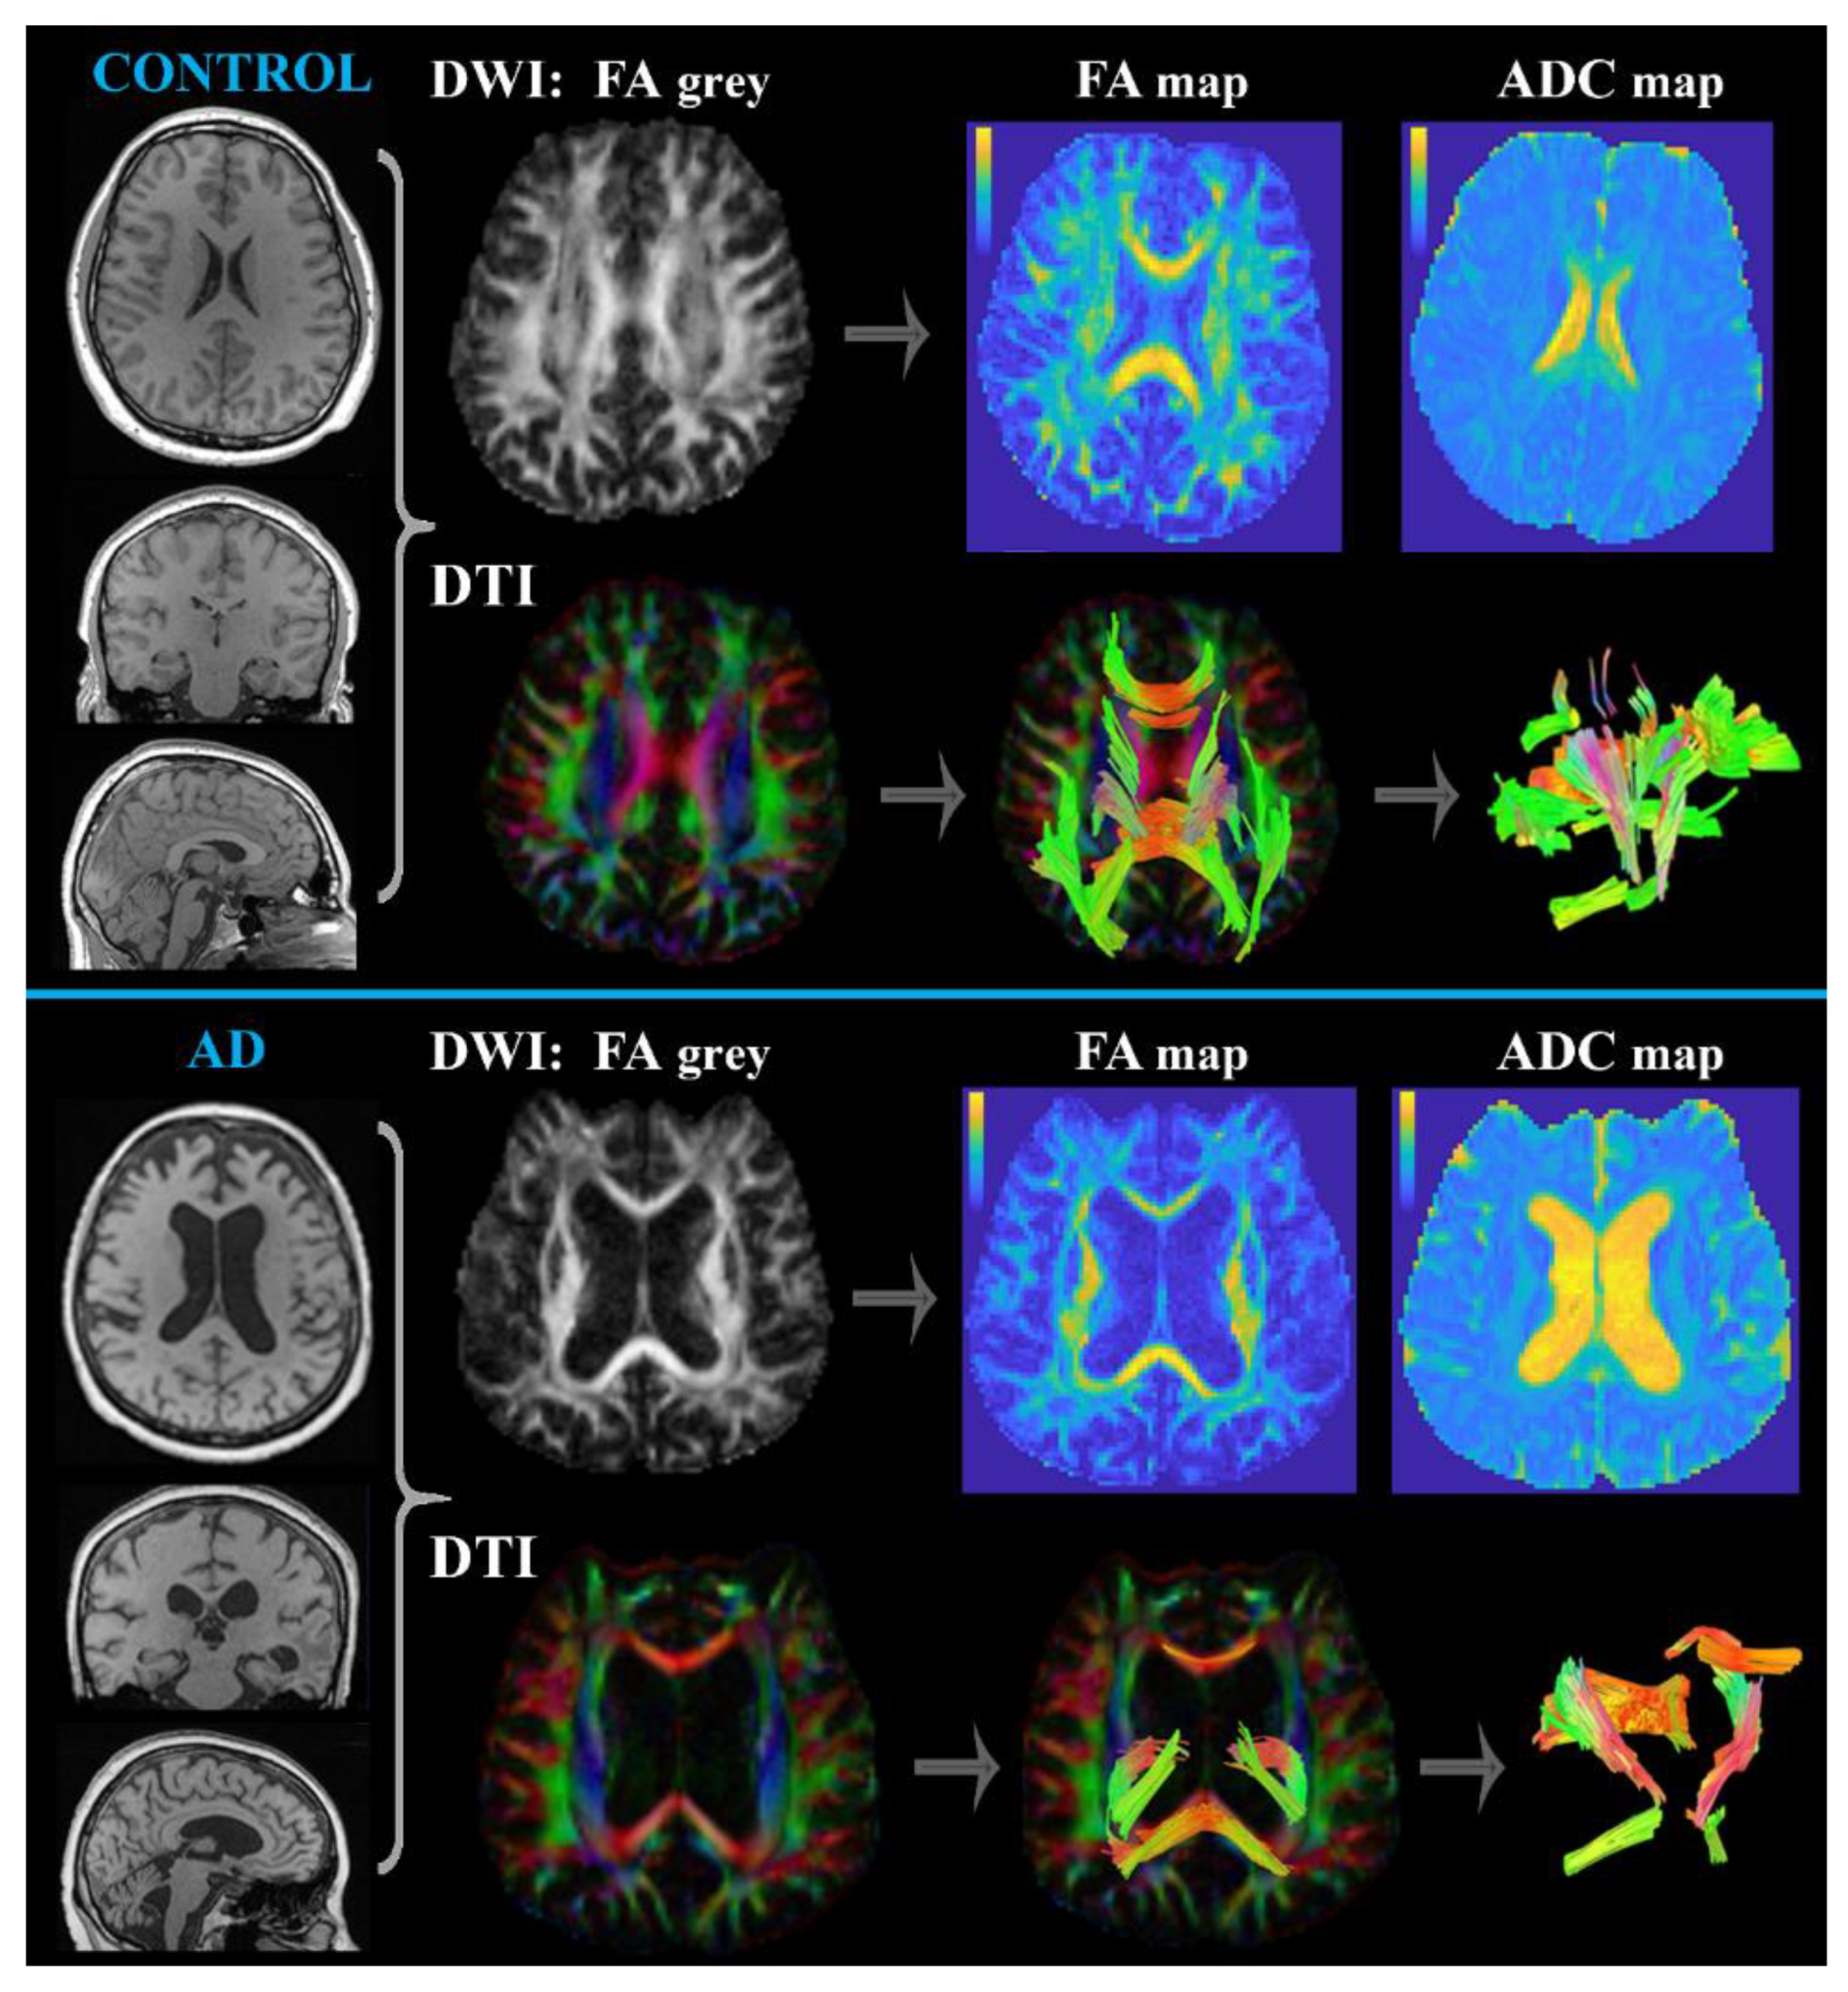

Diffusion MRI (DWI and DTI)

- Drake-Perez, M.; Boto, J.; Fitsiori, A.; Lovblad, K.; Vargas, M.I. Clinical applications of diffusion weighted imaging in neuroradiology. Insights Imaging 2018, 9, 535–547. [Google Scholar] [CrossRef]

- Gaddamanugu, S.; Shafaat, O.; Sotoudeh, H.; Sarrami, A.H.; Rezaei, A.; Saadatpour, Z.; Singhal, A. Clinical applications of diffusion-weighted sequence in brain imaging: Beyond stroke. Neuroradiology 2022, 64, 15–30. [Google Scholar] [CrossRef]

- Harrison, J.R.; Bhatia, S.; Tan, Z.X.; Mirza-Davies, A.; Benkert, H.; Tax, C.M.W.; Jones, D.K. Imaging Alzheimer’s genetic risk using diffusion MRI: A systematic review. Neuroimage Clin. 2020, 27, 102359. [Google Scholar] [CrossRef] [PubMed]

- Baliyan, V.; Das, C.J.; Sharma, R.; Gupta, A.K. Diffusion weighted imaging: Technique and applications. World J. Radiol. 2016, 8, 785–798. [Google Scholar] [CrossRef]

- Huisman, T.A. Diffusion-weighted and diffusion tensor imaging of the brain, made easy. Cancer Imaging 2010, 10, S163–S171. [Google Scholar] [CrossRef] [PubMed]

- Perea, R.D.; Rabin, J.S.; Fujiyoshi, M.G.; Neal, T.E.; Smith, E.E.; Van Dijk, K.R.A.; Hedden, T. Connectome-derived diffusion characteristics of the fornix in Alzheimer’s disease. Neuroimage Clin. 2018, 19, 331–342. [Google Scholar] [CrossRef]

| diffusion MRI (DWI, DTI) | demyelinated axons; damaged nerve tracks; 3D visualization of neural pathways | pitfall of mucinous or hemorrhagic lesions; highly motion sensitive |